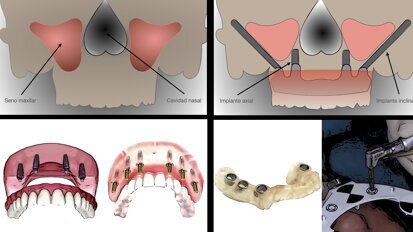

Carga inmediata o diferida en el maxilar totalmente edéntulo

Tres expertos franceses explican que la efectividad entre la carga inmediata y la carga diferida de implantes en el paciente con maxilar totalmente ...